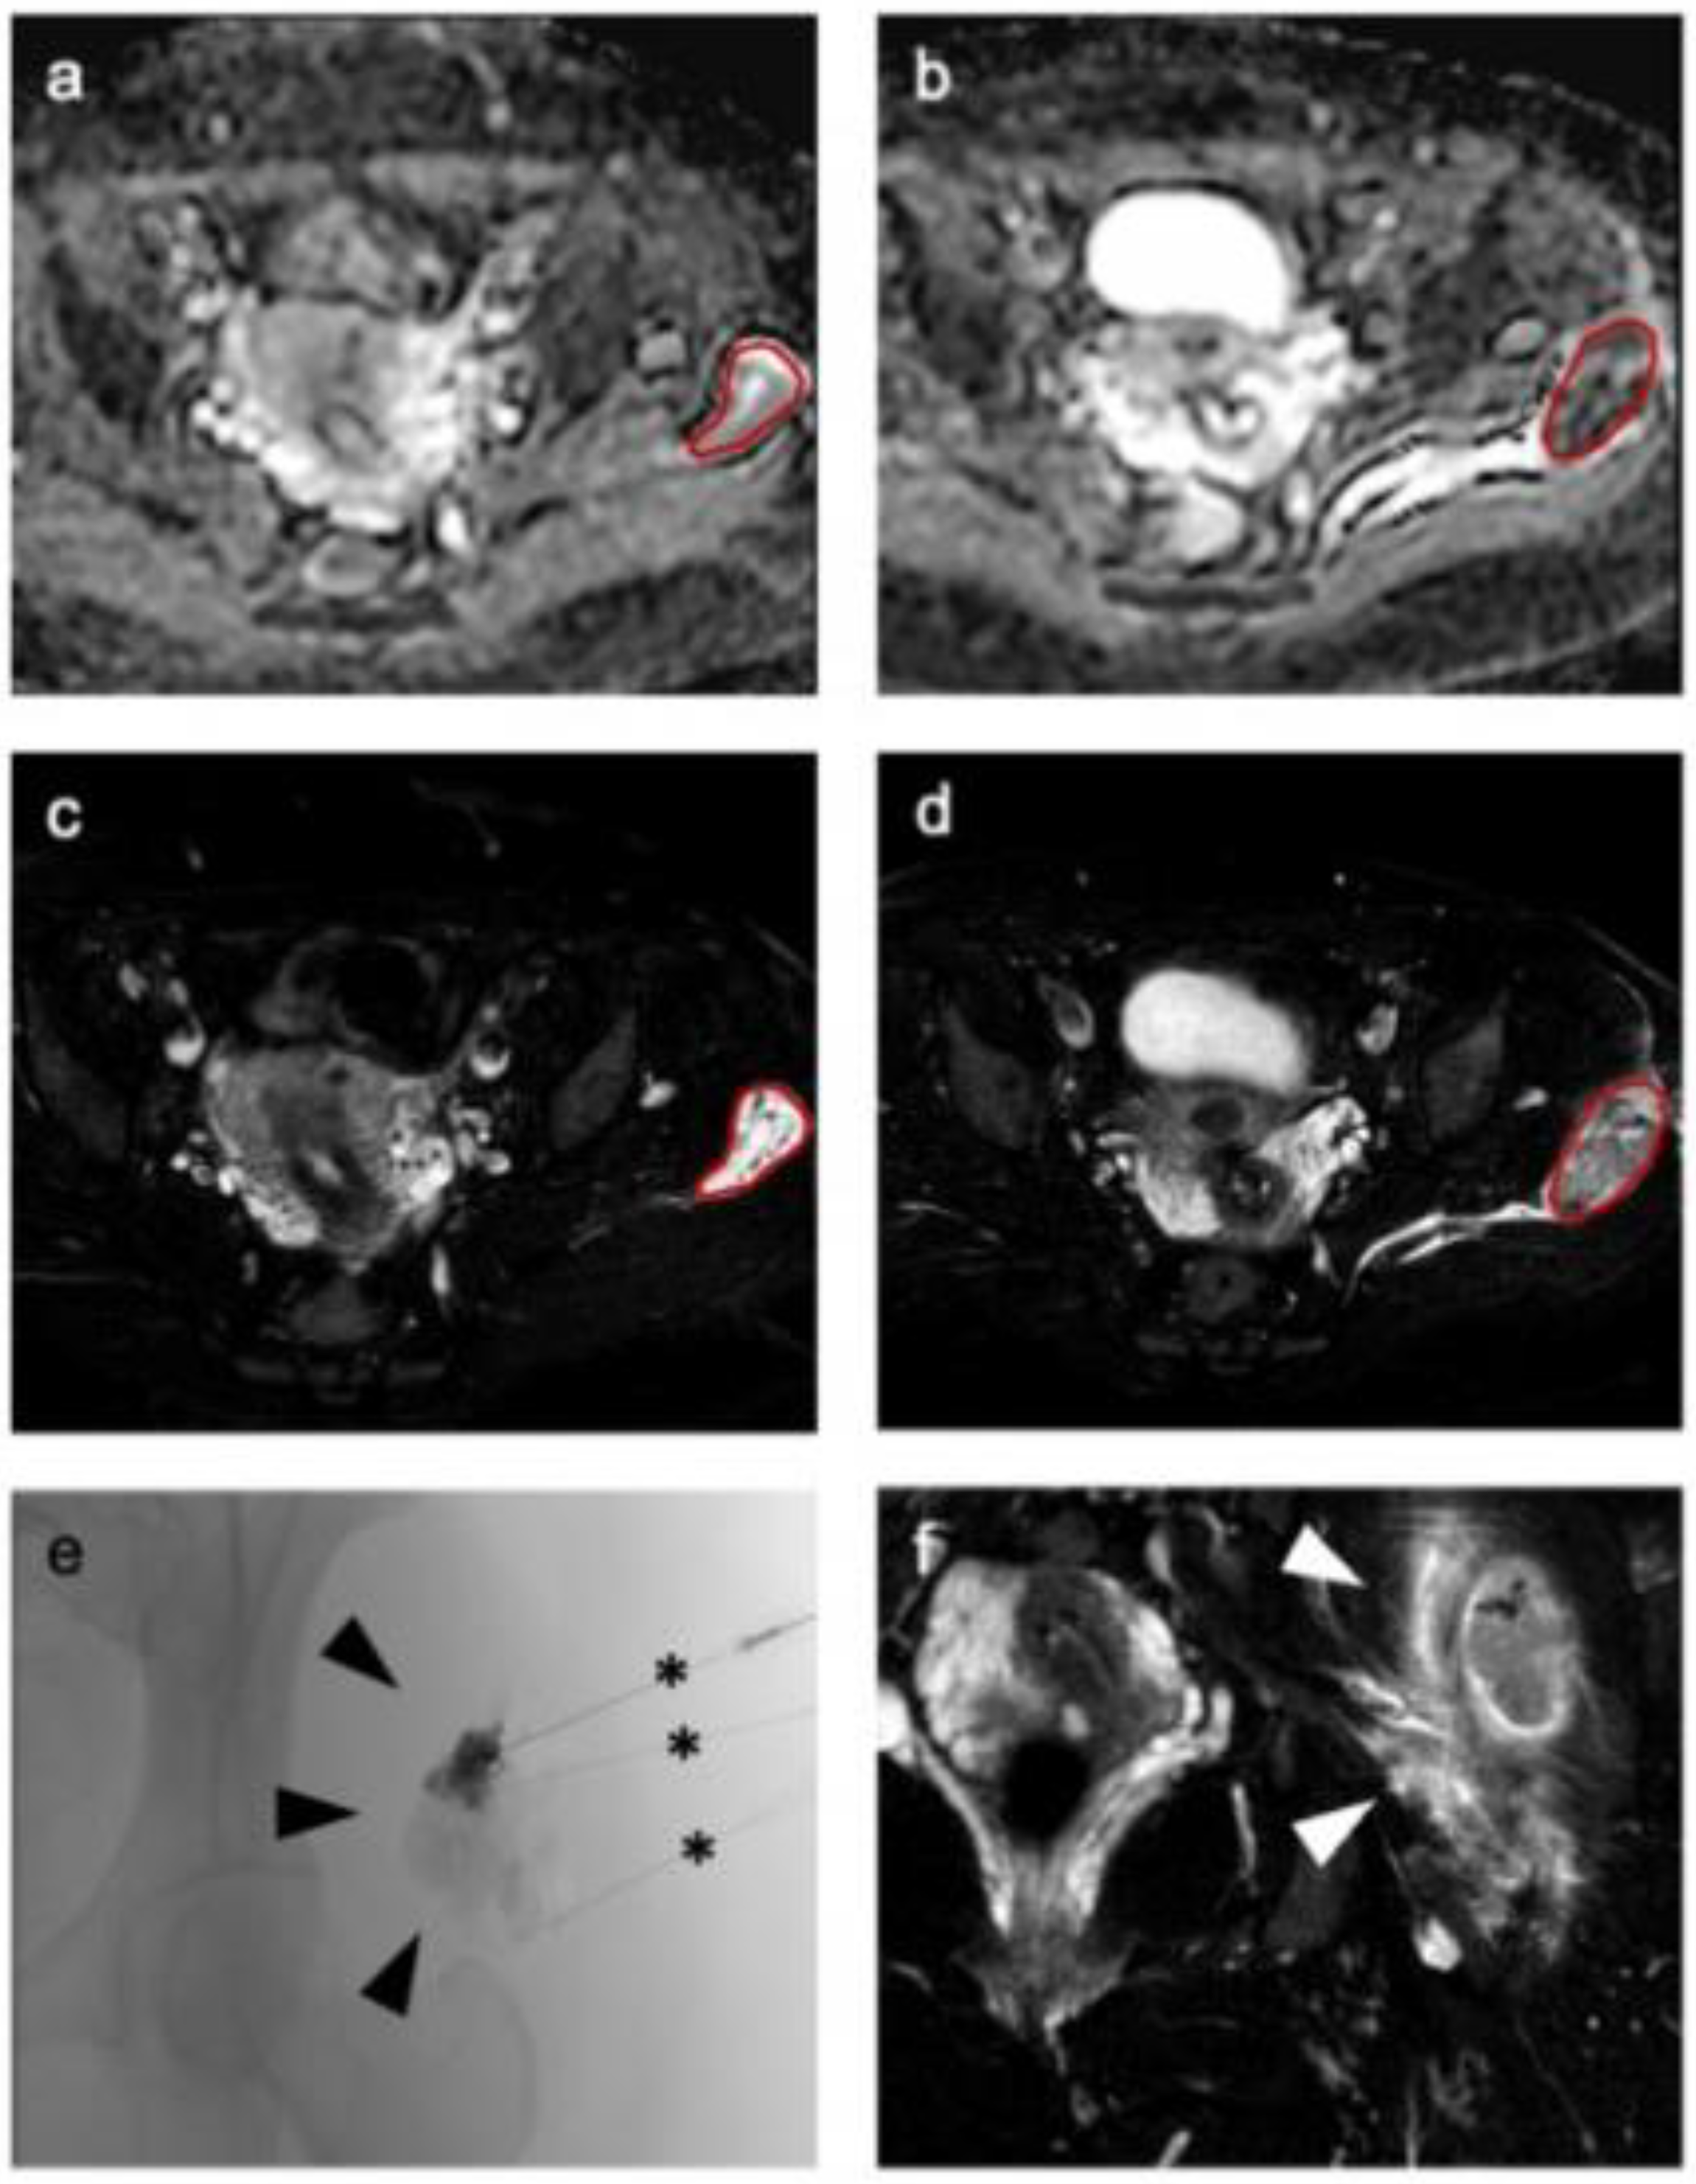

2.2. MRI Examination

2.3. Interventional Therapy

2.5. Image Analysis and Radiomic Feature Extraction